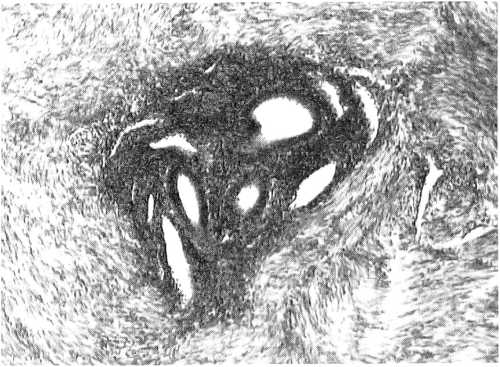

Диагноз «аденомиоз» выставляли на основании визуализации при микроскопии эндометриоидных гетеротопий в толще миометрия (рис. 1) при обнаружении железистого или стромального компонентов либо при их сочетании.

Рис. 1. Эндометриоидные включения в миометрии. Железистый и стромальный компоненты. Микрофотография. ×200, гематоксилин и эозин